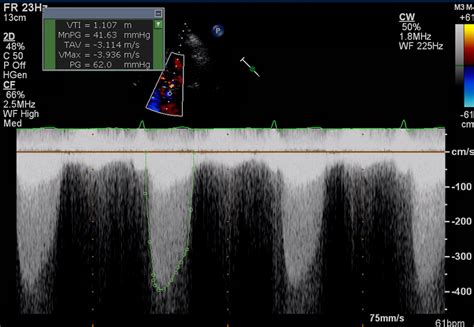

Physicians typically diagnose Severe Aortic Stenosis through a combination of physical examinations and advanced imaging technologies. The most common diagnostic tool is the echocardiogram, which provides a real-time visualization of the valve’s movement and measures the severity of the obstruction.

Transthoracic Echocardiogram (TTE) Valve area, pressure gradient, and left ventricular function.

• severe aortic stenosis gradient